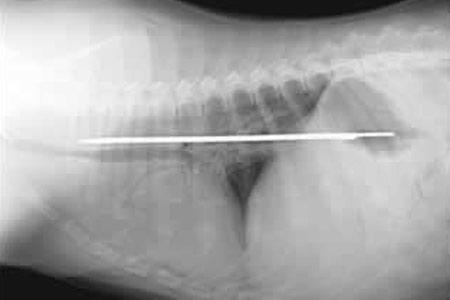

Şoke eden röntgen filmleri

Bu röntgen filmleri görenleri şaşkına çeviriyor!